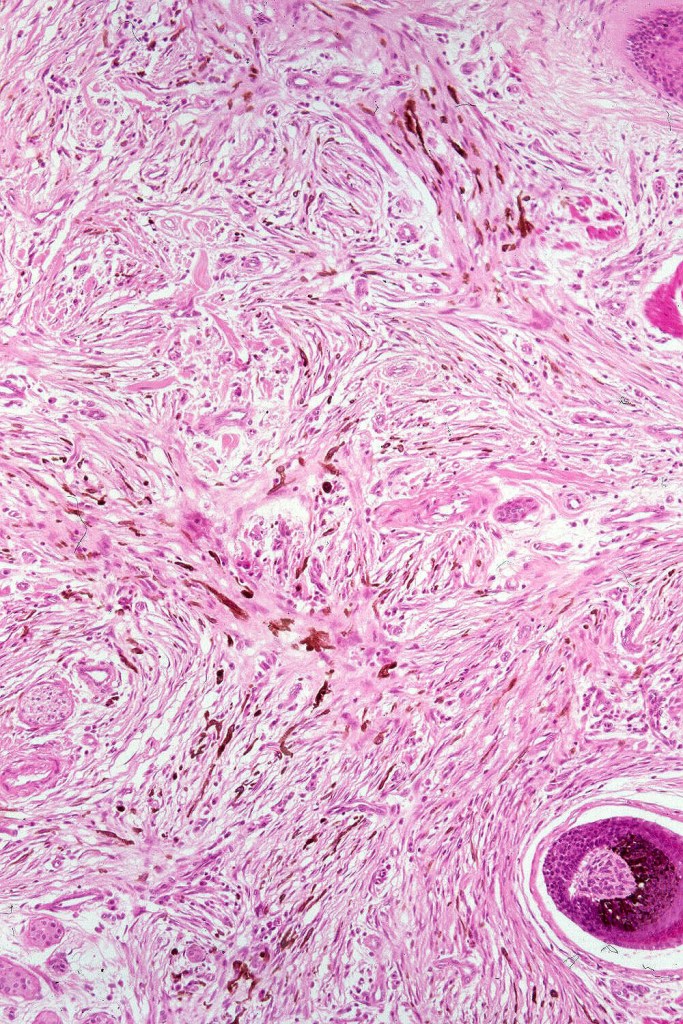

Histologically, it is characterized by a dense population of spindled, dendritic melnanocytes & melanophages with variable fibrosis. It may sometimes represent a component of a combined nevus. Mitotic activity is not usually present and pleomorphism is absent (see atypical blue nevus below). Involvement of the arrector pili muscle is not uncommon.

•Most characteristic is the dumbbell silhouette although a plague morphology may also be encountered

•Admixture of spindle cells, pigmented bipolar or dendritic cells & melanophages

•An alveolar pattern is characteristic particularly with clear cell nodules

•Stromal fibrosis, myxoid change, vascular hyalinization with cyst formation are often seen

•Some tumors are composed spindle cells in a fascicular or neuronevoid pattern

•Perineural involvement may be seen

Histologically it presents in varying proprtions of banal and blue nevus accompanied by scattered dendritic cells associated with neurofibroma-like spindle cells and Schwann cell nodules with Meissner corpusces surrounded by sustentacular EMA positive cells. The lesion typically ensheathes the hair follicles.